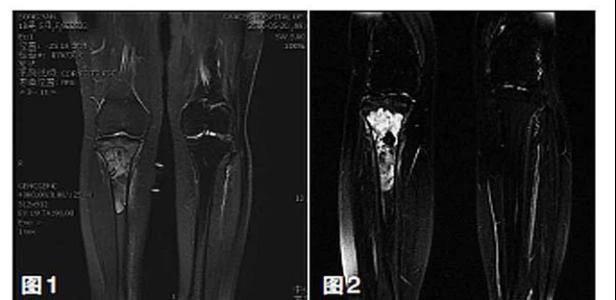

新輔助化療的目的是盡早殺滅遠處微小轉(zhuǎn)移灶,縮小腫瘤及周圍炎性水腫反應(yīng)區(qū),以利于后續(xù)的保肢手術(shù);觀察腫瘤對化療的敏感性,為進一步指定個體化的術(shù)后化療方案奠定基礎(chǔ)。骨肉瘤新輔助化療下的保肢治療如下圖所示: